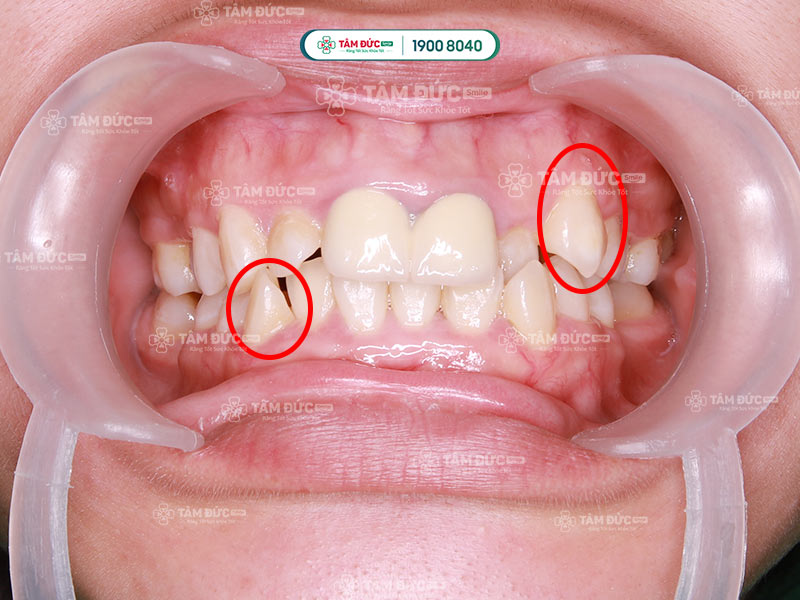

Răng nanh mọc lệch là một trong những vấn đề răng miệng phổ biến ở cả trẻ em và người trưởng thành. Tình trạng này thường do thiếu chỗ trên cung hàm, di truyền hoặc răng sữa không rụng đúng thời điểm, khiến răng nanh phải mọc lệch ra ngoài, chìa ra hoặc chen chúc với răng cửa. Không chỉ ảnh hưởng đến thẩm mỹ khuôn mặt, răng nanh mọc lệch còn gây khó khăn khi vệ sinh, lệch khớp cắn và thậm chí ảnh hưởng phát âm. Với đội ngũ bác sĩ chuyên sâu và giải pháp niềng răng hiện đại, Nha khoa Tâm Đức Smile cung cấp giải pháp điều trị răng nanh mọc lệch hiệu quả, đảm bảo khôi phục hàm răng đều đẹp và chức năng ăn nhai toàn diện.

Răng nanh mọc lệch là khi răng nanh không nằm đúng vị trí và mọc không đều so với các răng còn lại. Điều này có thể làm thay đổi hình dáng tổng thể của hàm răng, làm ảnh hưởng thẩm mỹ nụ cười và làm giảm chức năng nhai.

Răng nanh mọc lệch có thể làm sai khớp cắn, cản trở việc vệ sinh răng miệng và tạo ra áp lực không đều trên các răng khác. Răng nanh mọc lệch có thể xuất hiện dưới nhiều dạng khác nhau, dưới đây là một số kiểu phổ biến:

- Răng nanh mọc lệch lên trên (răng khểnh)

- Răng nanh mọc lệch vào trong

- Răng nanh mọc chen chúc

- Răng nanh mọc lệch về bên

- Răng nanh mọc chệch xuống dưới

Răng nanh mọc lệch